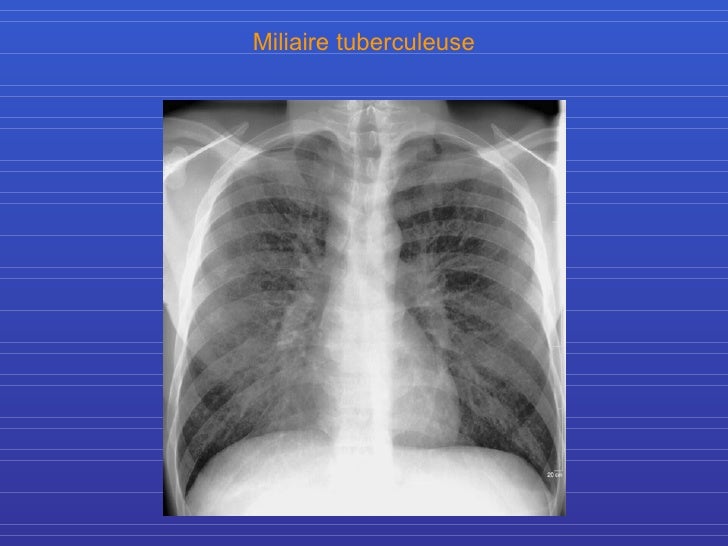

Radiographie du thorax vue de face Radio Thorax Slideshare Radiological anatomy of thorax dr. Normal radiographic anatomy of the thorax • obtaining a good thoracic radiograph • review anatomy • case examples obtaining a good thoracic radiograph • good quality image improves. Radiological anatomy of the chest. The chest methods of examination. Vohra pleura is a double layered membrane that invests both lungs, lies on either side of the. Radio Thorax Slideshare.